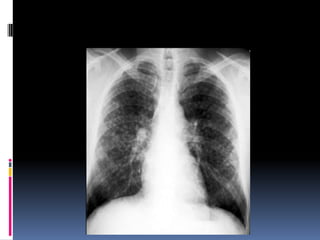

Penetration / Exposure

 Able to see ribs

through the heart

 Barely see the

spine through the

heart

 Pulmonary vessels

can be traced

nearly to the edges

of the lungs

Penetration / Exposure Able to see ribs through the heart  Barely see the spine through the heart  Pulmonary vessels can be traced nearly to the edges of the lungs